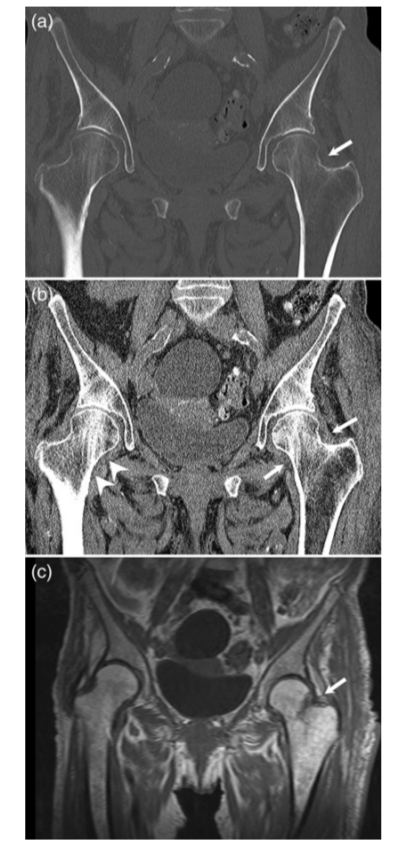

病例4股骨颈骨折,在CT横断面骨窗上未见明显液体分层(a),在软组织窗(b)可见高密度血肿影(箭头所示,CT值为50HU)。

病例5股骨颈骨折,在CT横断面软组织窗上可见在髂腰肌内出现积脂血症表现。

病例6 一例82岁髋部外伤患者,非移位股骨颈骨折,在CT横断面可见积脂血症,MR证实股骨颈骨折。关节积脂血症在非移位股骨颈骨折的识别中作用明显。